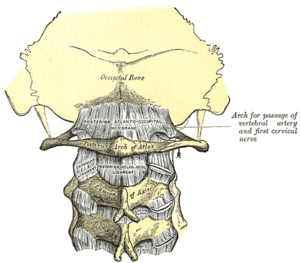

- Sciatica – refers to pain, weakness, numbness, or tingling in the leg. It is caused by injury to or pressure on the sciatic nerve.